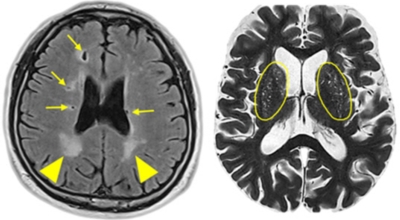

뇌경색의 가장 흔한 원인은 고혈압, 당뇨, 고지혈증 등으로 인해 뇌에 혈액을 공급하는 혈관에 뇌혈류가 차단되는 경우와 그 밖에심장 부정맥, 심근경색의 후유증 등으로 인해서 심장에 혈액이 응고된 상태가 되고 이 혈전이 혈류를 따라 이동하다가 뇌혈관을 막아 뇌졸중이 나타나는 경우도 있어요.

뇌경색 초기증상의 가장 유명한 것은 피로감인데요 특별한 질환이나 증상이 없다가 갑작스럽게 피로감이 느껴진다면 뇌경색을 의심해보아야 해요. 뇌경색이 발생하면 콜레스테롤과 노폐물이 혈관을 막고, 뇌에 공급되어야 하는 피와 영양분이 제대로 공급되지 않아서 항상 피곤하고 피로한 증상이 일어날 수 있습니다.